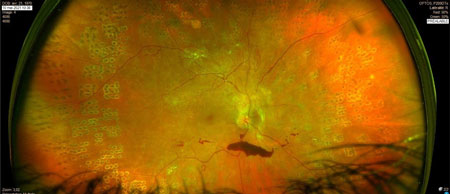

DR tractionnel préop

DR tractionnel post op

préop HIV + rétrohyaloïdienne

post op idem

HIV préop

HIV post op